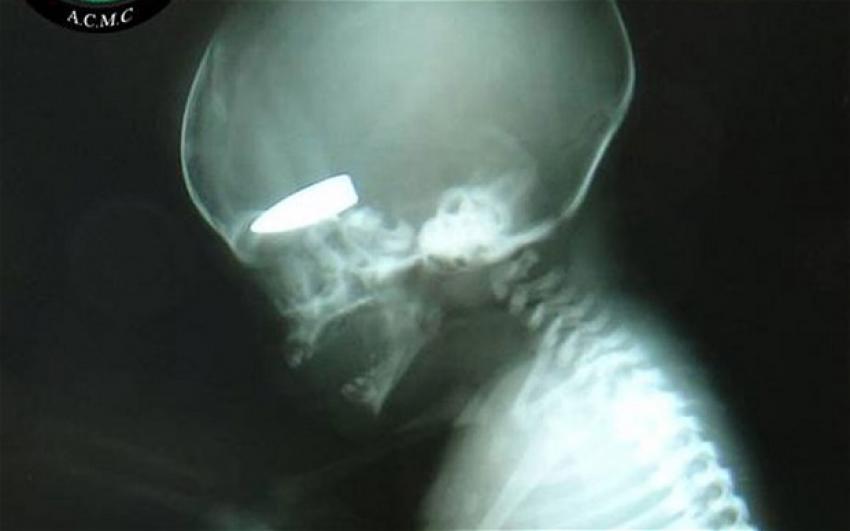

ΣΟΚ από Συρία! Έμβυο με σφαίρα στο κρανίο - Στοχεύουν έγκυες γυναίκες!

“επιβραβεύονται” μ΄ αυτό με μερικά πακέτα τσιγάρα. Η αποκάλυψη που δημοσιεύεται στην βρετανική εφημερίδα Telegraph, είναι ανατριχιαστική και συνοδεύεται από τη φωτογραφία ενός εμβρυου στο οποίο έχει “καρφωθεί” η σφαίρα ενός ελεύθερου σκοπευτή.

Σε μία μόνο ημέρα περισσότερες από έξι έγκυες γυναίκες είχαν χτυπηθεί από πυρά ελεύθερων σκοπευτών. Οι περισσότερες επιβίωσαν όχι όμως και τα έμβρυα.

Η βρετανική εφημερίδα δημοσιεύει τη φωτογραφία της ακτινογραφίας που δείχνει ένα έμβρυο να έχει σφηνωμένο στο κρανίο του μια σφαίρα .